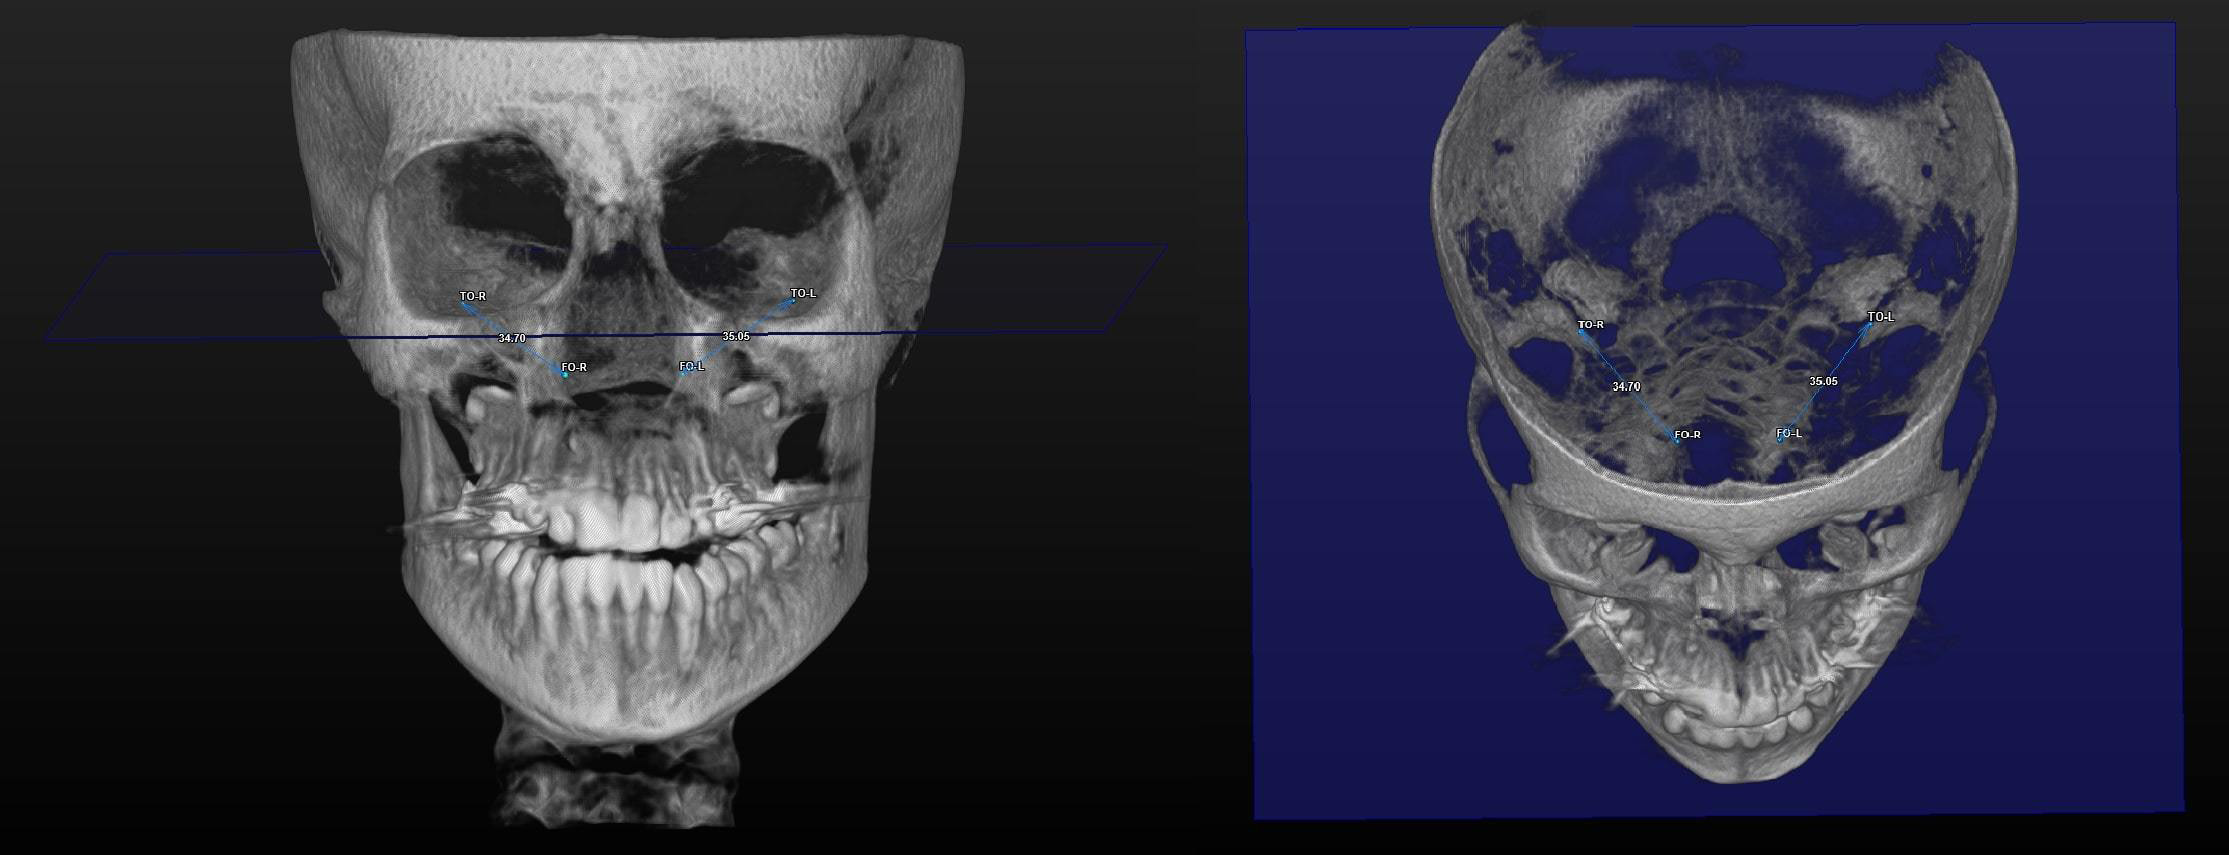

All 3D CBCT images were obtained with patients in a standing position using a CBCT device (ProMax® 3D Mid; Planmeca, Helsinki, Finland). The settings were as follows: 94 kVp; 14 mA; and 27 s. The images were consistent with the field of view (FOV) (20.0 cm × 20.0 cm × 10.2 cm) and voxel size (0.600 mm). The assessment of all CBCT images was conducted in 3D by a single clinician. The SimPlant® O&O image software (Materialise Dental N.V., Leuven, Belgium) was used for 3D image evaluation. The 3D morphological linear and angular parameters are listed in Table 1. The 3D morphological ET traces are displayed in Figure 1, Figure 2, Figure 3.

The comparison of the 3D linear and angular data is presented in Table 3. The mean right ET lengths were 36.26 ±3.10 mm at T0 and 36.13 ±3.08 mm at T1. Before and after RME, the mean left ET lengths were 36.82 ±2.98 mm and 36.82 ±3.12 mm, respectively. The right and left ET lengths did not differ significantly between T0 and T1 (p = 0.513 and p = 0.978, respectively). The mean right ET angle was 22.23 ±3.72° before RME and 22.82 ±4.06° after RME. At T0, the mean left ET angle was 22.33 ±4.22°. At T1, the mean left ET angle was 22.74 ±3.84°, indicating a non-significant difference (p = 0.077 and p = 0.184, respectively). The right auditory tube angle at T0 exhibited a significant increase compared to that at T1 (p = 0.000). The mean left auditory tube angles were 127.87 ±3.28° at T0 and 127.53 ±3.45° at T1 (p = 0.197).

Dinç et al. compared the ET angle and length in healthy subjects and those with otitis media. The ET angles in healthy individuals were 23.0° in females and 24.3° in males.25 The Frankfort horizontal plane was used when measuring ET angles. The angles in our study were slightly lower. In other studies, the mean ET angles with the horizontal palatal plane averaged 34–36° in adults.26, 27, 28 In adolescents, the ET angle with the Frankfort horizontal plane was approx. 22°. The difference may reflect age-related changes and the use of reference planes. The ET angle remained constant after RME on both sides. No prior study has measured the effect of RME on 3D ET angles. Therefore, there was no basis for comparison. We expected that any changes would be similar; symmetrical RME was applied to the mid-palatal suture. No differences in right and left ET length were observed between T0 and T1 (right: 36.26 ±3.10 mm at T0 and 36.13 ±3.08 mm at T1, left: 36.82 ±2.98 mm at T0 and 36.82 ±3.12 mm at T1; p = 0.513 and p = 0.978, respectively). Using two-dimensional images, Bluestone et al. found that the ET length increased as children grew, attaining a final size of 31–38 mm at approx. 7 years of age.12 Takasaki et al. used conventional CT to compare the ET length between children and adults; the ET length in children was 38 mm and 43 mm in adults.28 The CBCT data obtained in the current study was slightly different, presumably due to the imaging modalities. Ha et al. noted that the ET lengths revealed by conventional CT and CBCT differed due to subjects’ positioning, whether in a supine or seated posture.29 Ultra-low-dose CBCT has been demonstrated to optimally detect morphological structures and is associated with reduced radiation, sharper imaging and briefer viewing than CT. Many studies have shown that RME consistently reduces conductive hearing loss and improves ET function in adolescents with maxillary transversal constriction.30 However, the present study found no significant effect of maxillary expansion on the ET length. There are 2 possible explanations for this state of affairs. Other studies have collected audiometric or tympanometric data; however, these studies did not include 3D CBCT linear and angular measurements. Secondly, RME inhibits the infection of the nasal and pharyngeal airways, which may contribute to a reduction in the incidence of otitis. Maxillary expansion improves conductive hearing loss and reduces the incidence of otitis media.